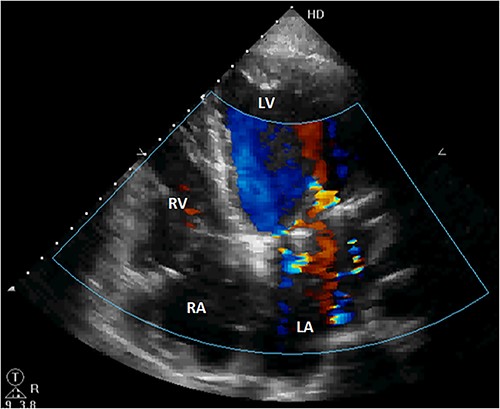

The patient was discharged after an uneventful postoperative course. The control TTE performed 2 weeks after the intervention showed that the right atrial shunt was gone (Fig. 6).

Postoperative TTE showing the disappearance of the right atrial shunt. RV, right ventricle; LV, left ventricle.